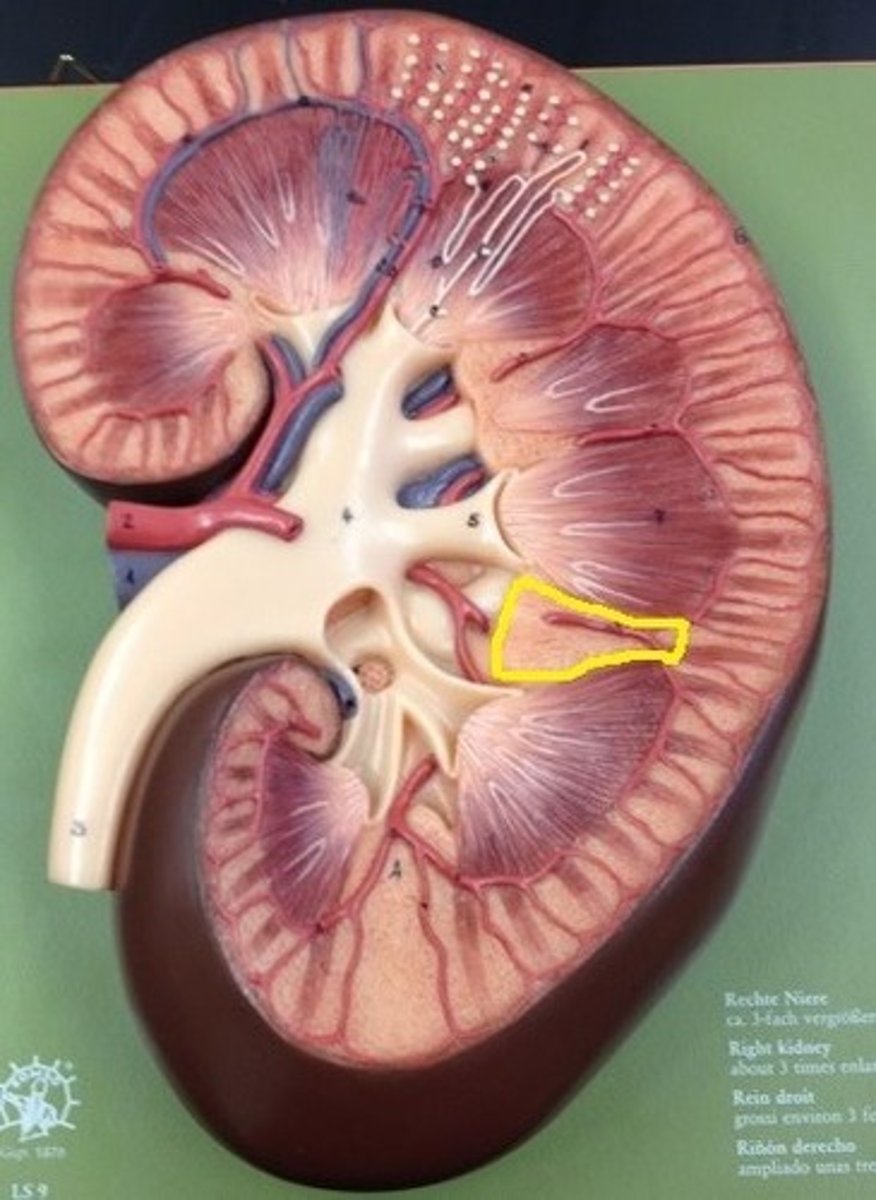

kidney

fibrous capsule

outer covering

renal cortex

renal medulla

renal papilla

major calyx

minor calyx

renal pelvis

renal pyramids

ureter

Pin in the middle

renal columns